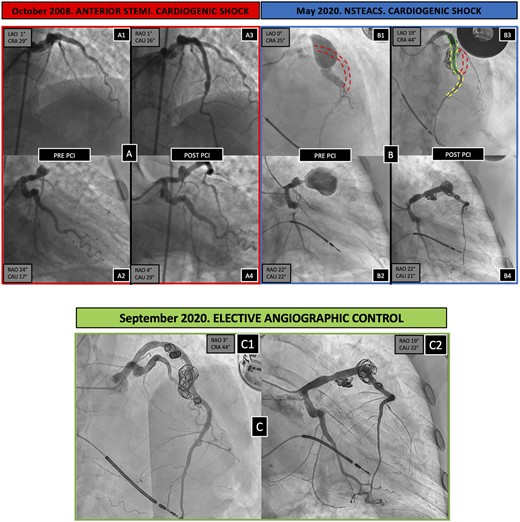

Emergency treatment of a giant coronary aneurysm: percutaneous intervention with coronary and peripheral tools, by Quadri et al Tools used: 1 IABP, 4 coronary DES, 8 coronary covered stents, 1 peripheral covered stent, and 6 coils academic.oup.com/eurheartj/arti…

Emergency treatment of a giant coronary aneurysm: percutaneous intervention with coronary and peripheral tools, by Quadri et al

Tools used: 1 IABP, 4 coronary DES, 8 coronary covered stents, 1 peripheral covered stent, and 6 coils

academic.oup.com/eurheartj/arti…